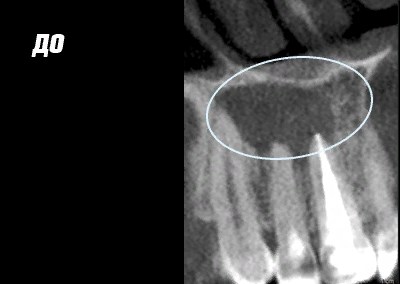

Работы врача

Фото ДО

Фото ПОСЛЕ

Наведите для просмотра

Лечение каналов